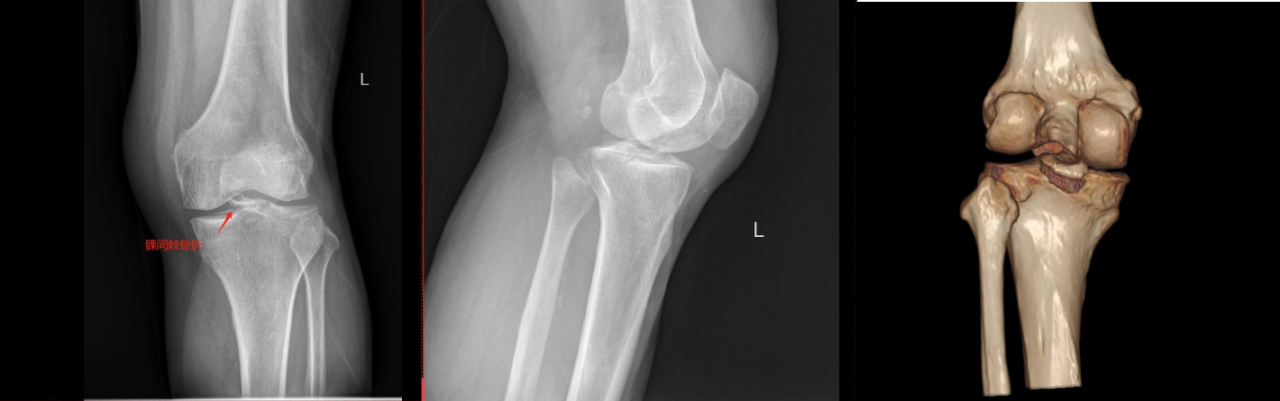

ⅢB型:多块撕脱骨折;合并半月板撕裂;BC>15mm;AE/AD≥1/2。

术式: 双袢(后叉前建立骨道)+骨道固定

合并内侧半月板放射裂

撕脱骨折、内侧半月板放射裂

半月板骨道固定、双袢固定撕脱骨折

术后X线片